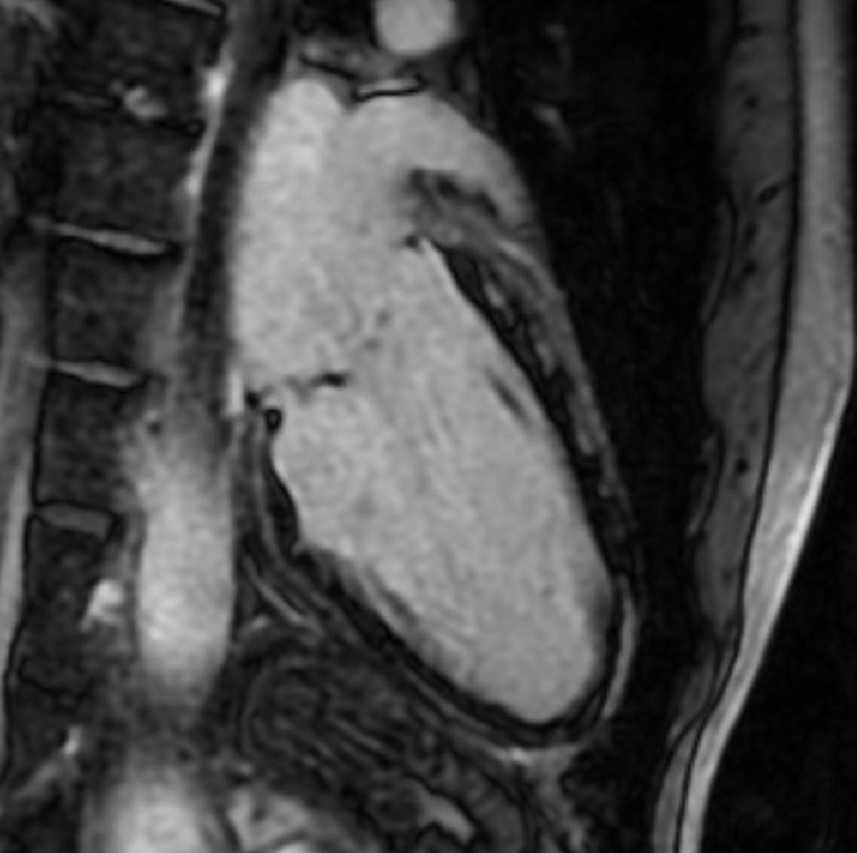

1-Beat Cardiac migliora la qualità diagnostica dell’angio-TC coronarica

L’angio-TC coronarica (CCTA) è uno strumento diagnostico essenziale per l’identificazione delle malattie coronariche, ma la sua affidabilità può essere compromessa nei pazienti con frequenza cardiaca elevata. Grazie ai progressi tecnologici, la modalità 1-Beat Cardiac consente ora di ottenere immagini di alta qualità anche in condizioni di elevata frequenza cardiaca.